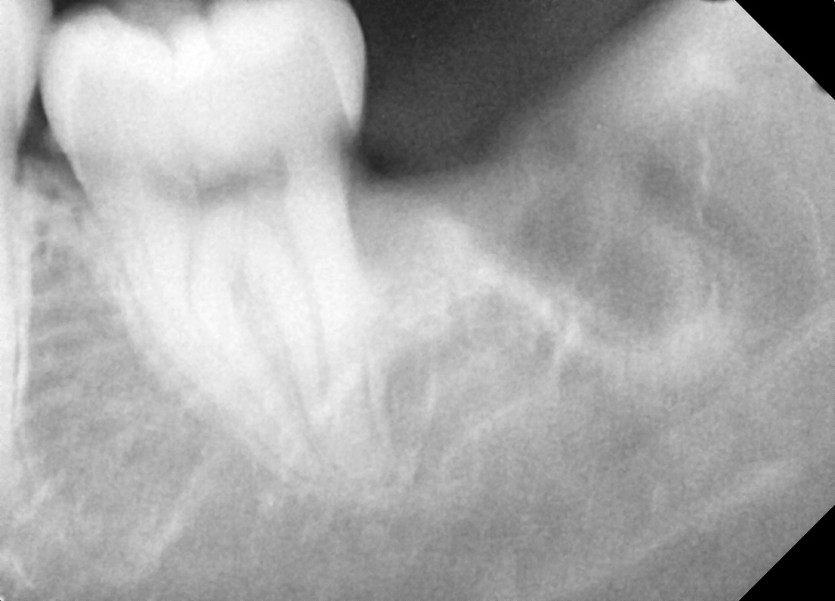

#28,38 사랑니 발치

구강외과 전문의가 당일 발치했습니다.